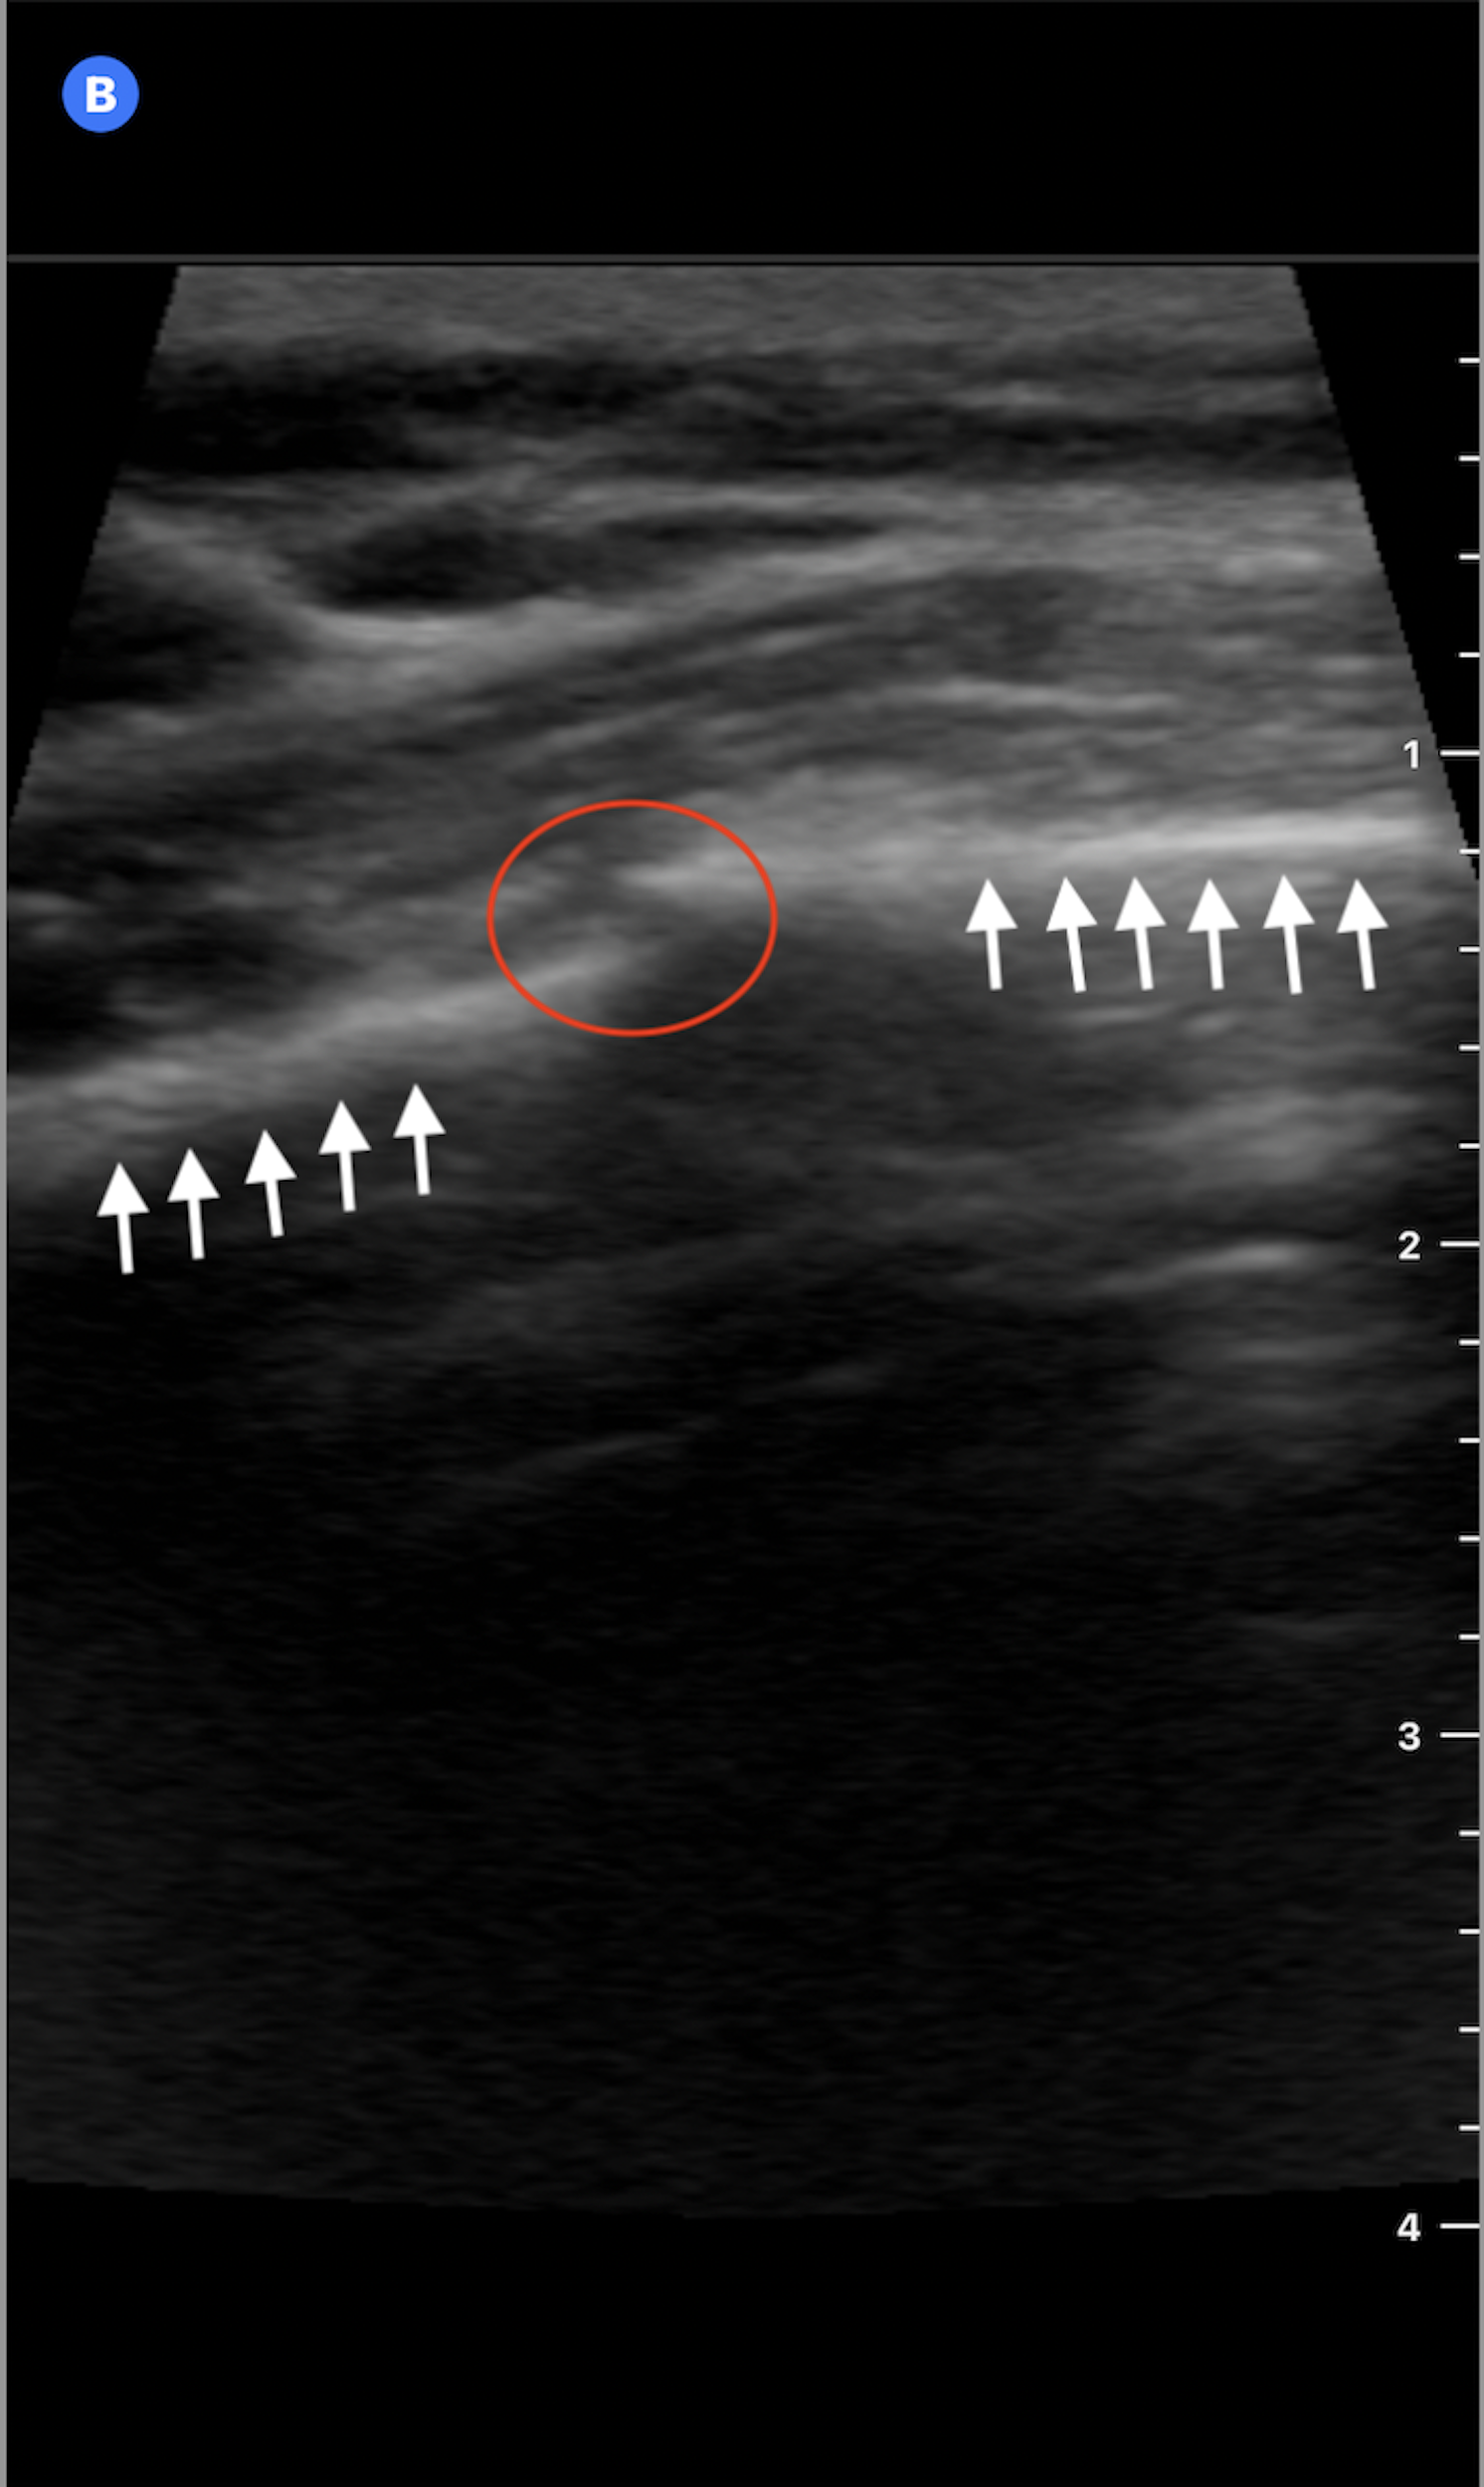

Using a high-frequency linear transducer, ultrasound evaluation of the left anterior chest wall in the longitudinal plane demonstrated disruption of the normally smooth hyperechoic rib cortex with a subtle step-off deformity. These findings were consistent with a non-displaced fracture of the fourth anterior rib.

Figure 2: Ultrasound image of the 4th anterior rib in the longitudinal plane shows linear hyperechoic bony cortex (white arrows) with a minimal step-off and discontinuity (red circle) consistent with a nondisplaced rib fracture.

In addition, no surrounding soft tissue hematoma was visualized. Lung sliding was present, and there was no pleural effusion, reducing concern for pneumothorax or hemothorax. Learn more about POCUS for pneumothorax in this article